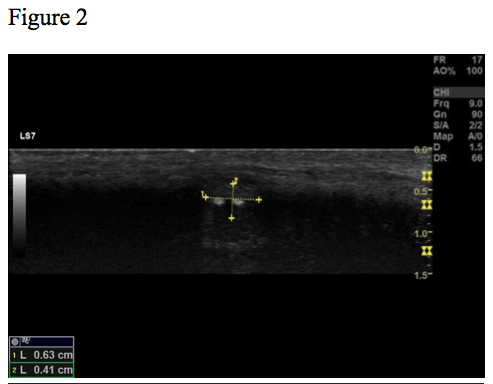

Figure 1, 2, 3 and 4 show the same hypoechoic lesion, a Peyronie’s plaque, in the penile connective tissue. The lesion has a well-defined circumference.

Figure 2. B-mode image. The size and the border of the lesion marked by yellow dotted lines. Lesion measures 0.6 x 0.4 cm.